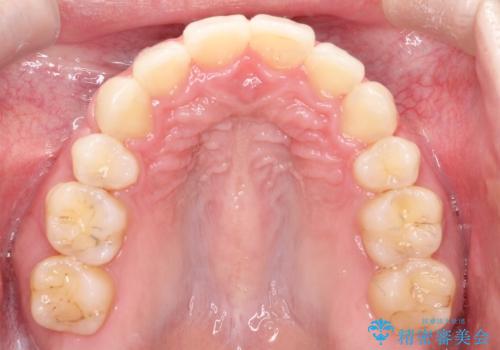

抜歯矯正により、前歯をしっかり下げることで口元がすっきりしました。